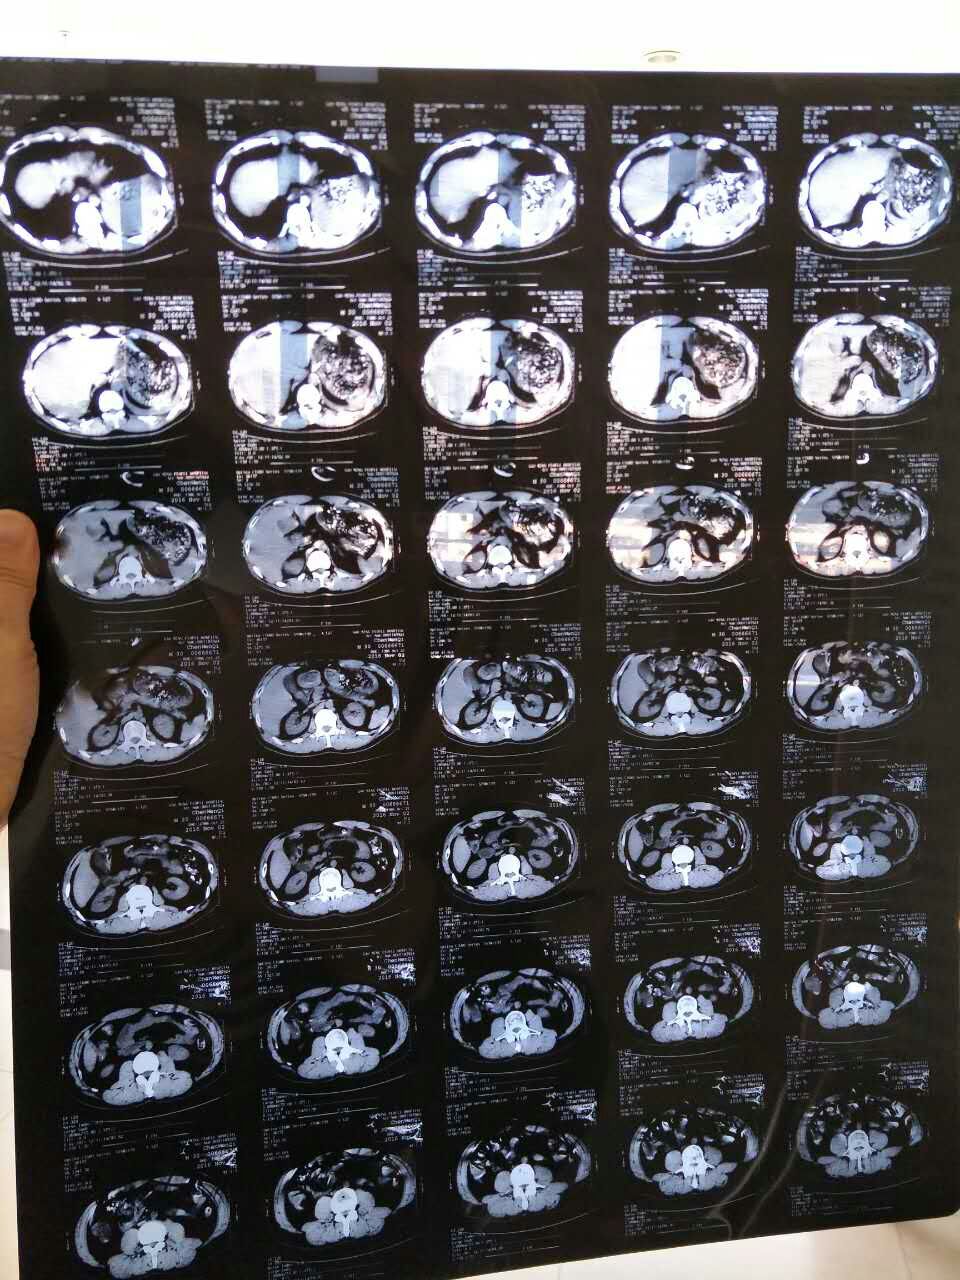

112日,凌晨1:21分,罗马协会·龙战盟硬汉,我的亲二哥,不幸自驾摩托遭遇车祸,从摩托车上撞飞10米至上空摔落铲滑,头部、胸部关节内脏等受到严重碰撞,其最严重是头部,当场不省人事。

紧急送往佛山市高明区人民医院后,医生进行了彻夜的手术抢救,从伤者头上摘除了10公分头骨。至今情况依然十分危急,至今昏迷不醒,目前仅靠昂贵的治疗,维持了生命体征。2天来,已经花掉了治疗费用8万多,现在每天还要花费6-8千元。

医生给予的治疗意见是:通过十到十五天的观察,进行药物治疗,病情稳定了再另作治疗,随后情况若有好转扔需再做一次头骨修复手术,胸骨手术,手骨手术,等。可是这需要数十万甚至未知数的费用来支撑。这对于这个经济条件不好的家庭来说,(四年前母亲脑瘤医药费已把所有积蓄用尽,去年才把所有债务还清,)实在是太庞大的数字了!如果凑不出这个钱,无疑,将要放弃的是这个年轻的生命。

(另附伤者的照片如下)